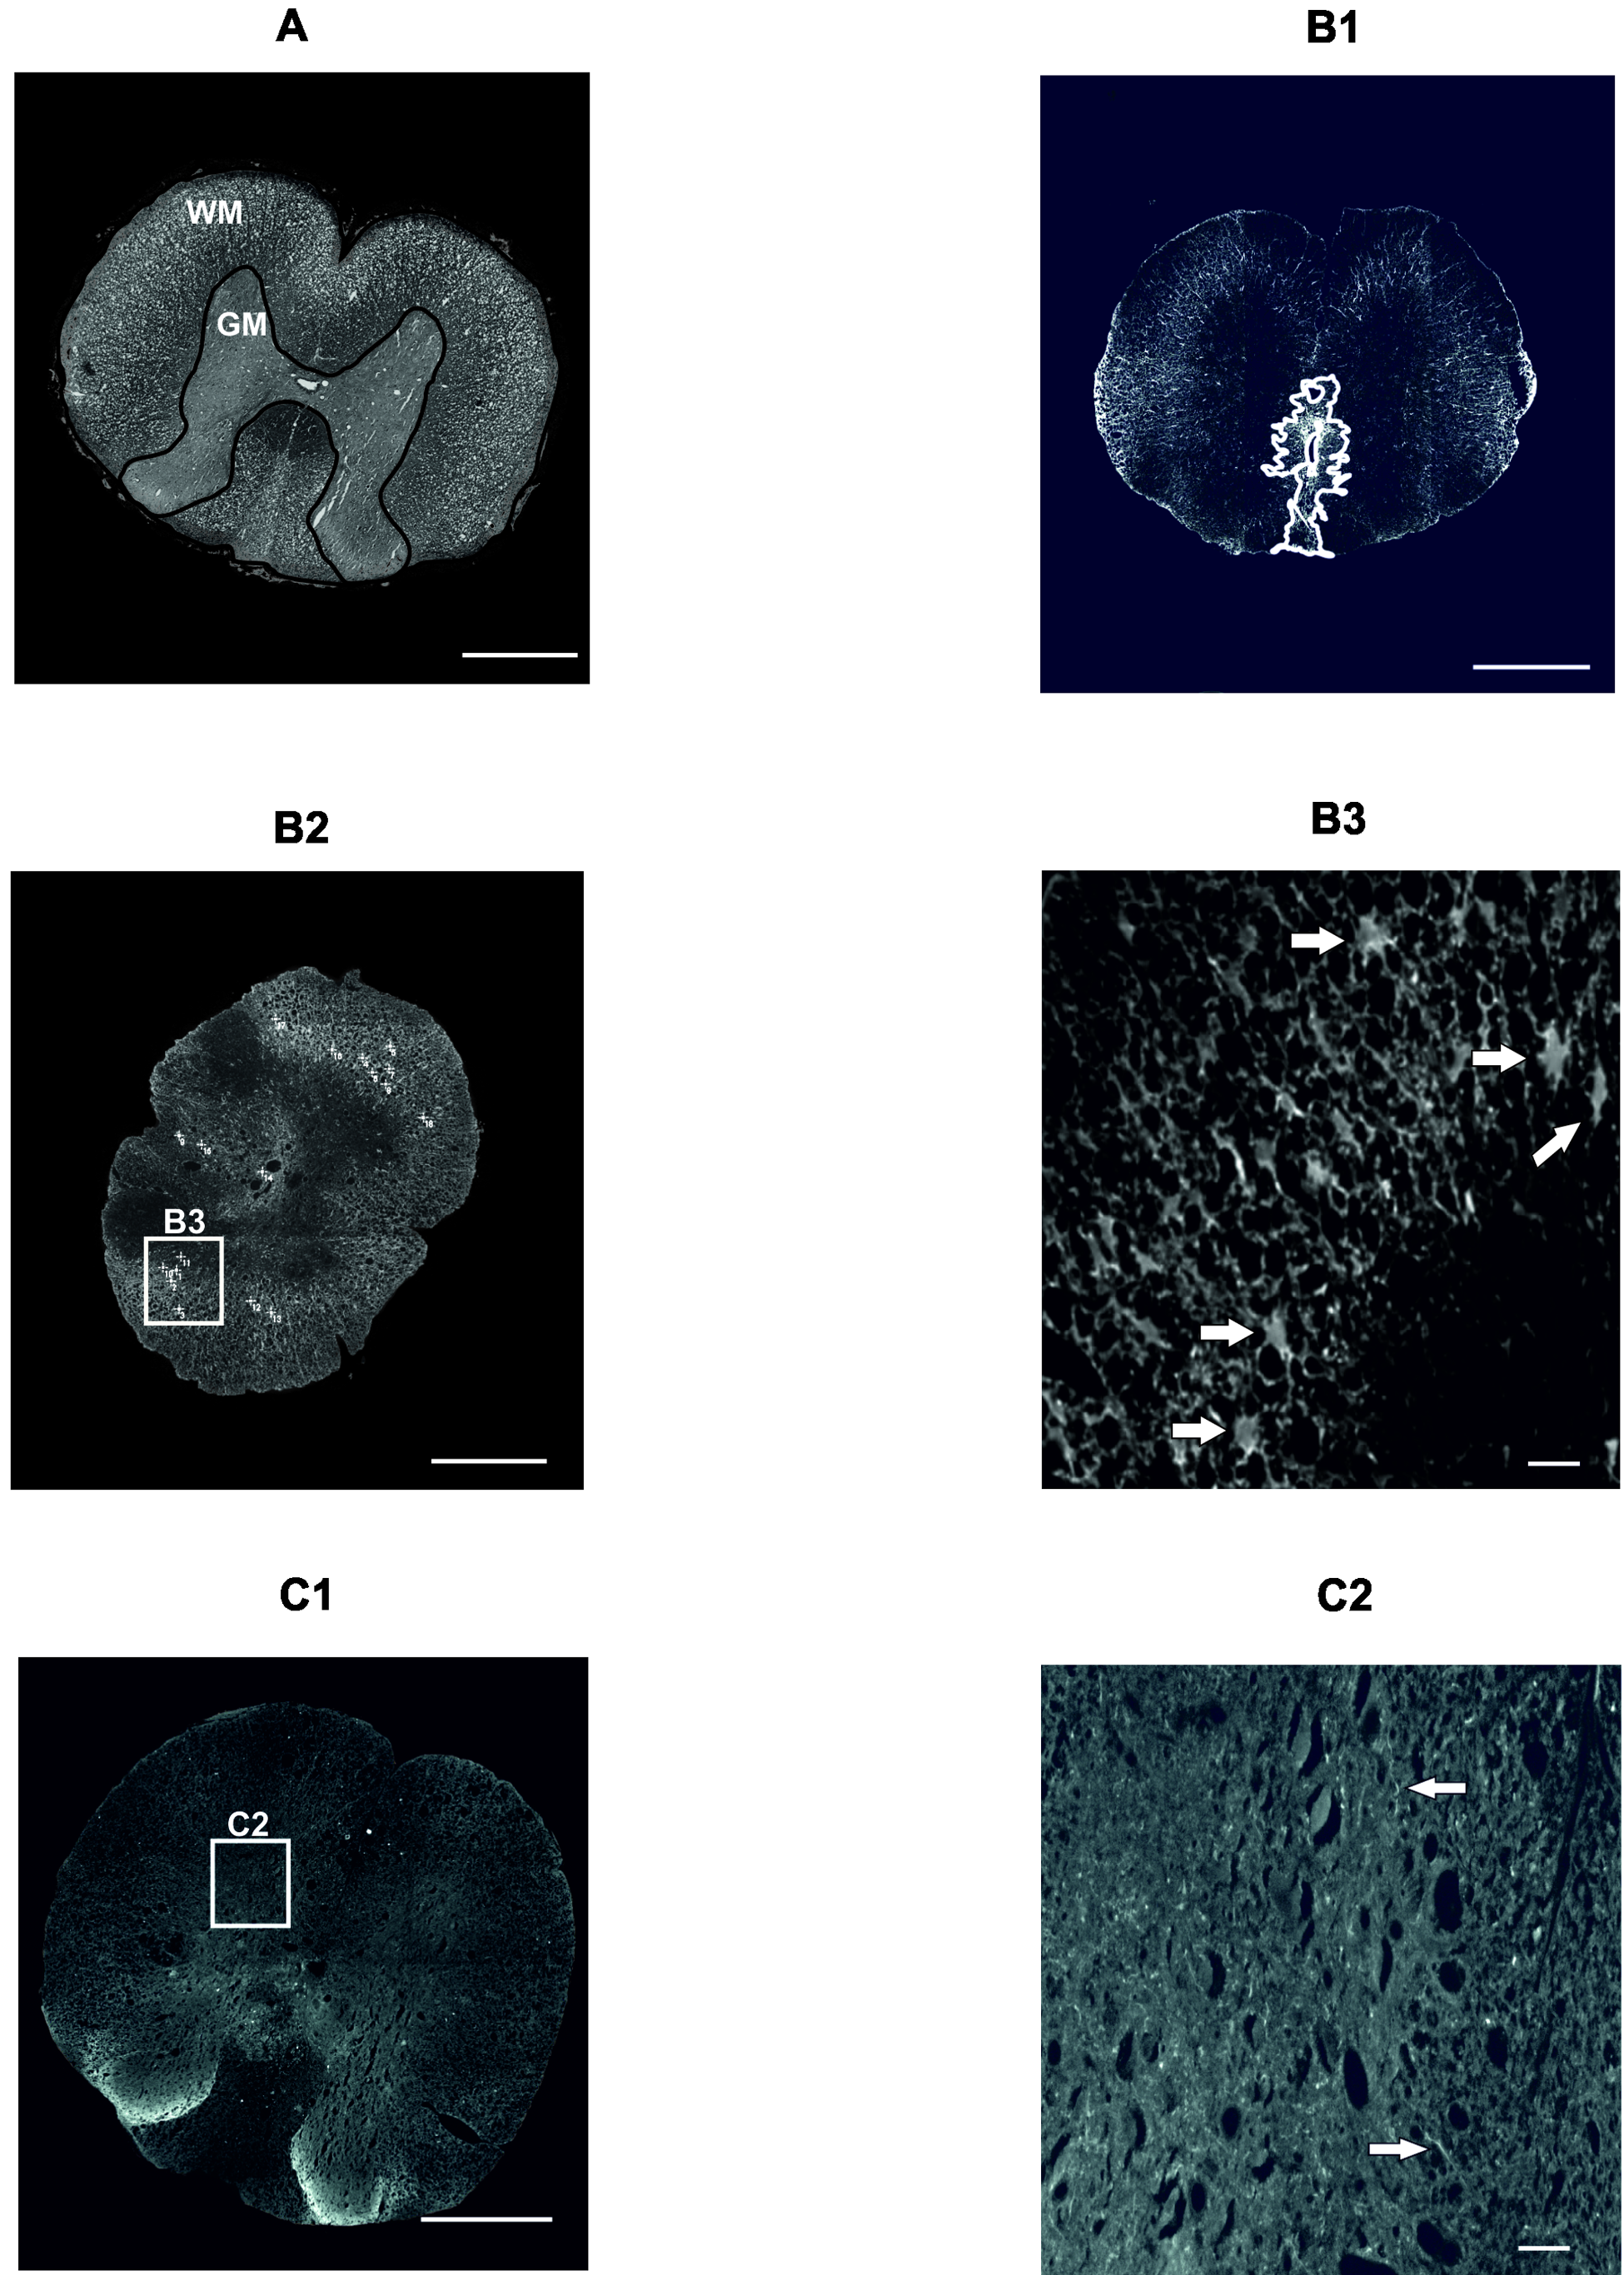

2.3.1. Gray and White Matter Sparing

2.3.2. Astrogliosis and Distribution of Protoplasmic Astrocytes

2.3.3. Axonal Sprouting

4.6. Histological and Immunohistochemical Analyses

4.6.1. Cresyl Violet-Luxol Staining

4.6.2. GFAP Staining

4.6.3. GAP43 Staining